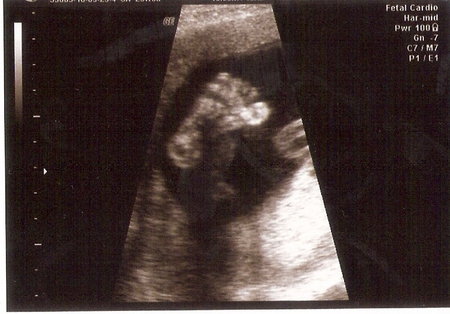

Сверху-ето сердечко малыша)))

Сделали очередное УЗИ.

Вес нашего мальчика 684 гр.Опять сказали,что крупненький,головка большая,соответственно и все остальное,ножки такие смешные,бьет ими внизу живота.Ну это я постоянно чувствую))).Мужское достоинство опять выделили)))По размерам он подходит почти на 25 недель.Значит ли это,что роды могут быть преждевременные или же просто малыш крупный?

Околоплодных вод нормальное количество.Не знаю почему,но за это я волновалась.

В этот раз мы были с Анютой,так что и она увидела братика.)))

Конечно,бесплатная проверка отличается от платной.Тут не поспоришь.Но все хорошо,А это самое главное.